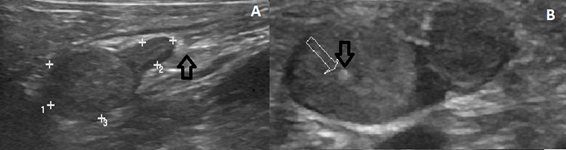

Abdominal ultrasound showed the presence of nodular images associated with the right and left adrenal glands (Figure 5). Although hyperadrenocorticism was suspected, baseline cortisol measurement was not performed since serum cortisol levels fluctuate throughout the day. Due to the severe clinical condition, the dexamethasone suppression test and adrenocorticotropic hormone (ACTH) stimulation test were not performed.

Figure 5 Abdominal ultrasound. A. Right adrenal gland (1.9cm long x 0.37cm thick at caudal pole x 1.0cm thick at cranial pole) with bulging cranial pole due the presence of hyperechogenic and slightly coarse nodulation (1.1cm x 0.97cm, arrow). B. Left adrenal gland with usual shape, curved contours and poles (2.0cm length x 0.72cm thickness at caudal pole x 0.84cm thickness at cranial pole) presence of hyperechogenic and slightly coarse nodulation (1.1cm x 0.82cm and 0.75 cm) at caudal pole (arrow).